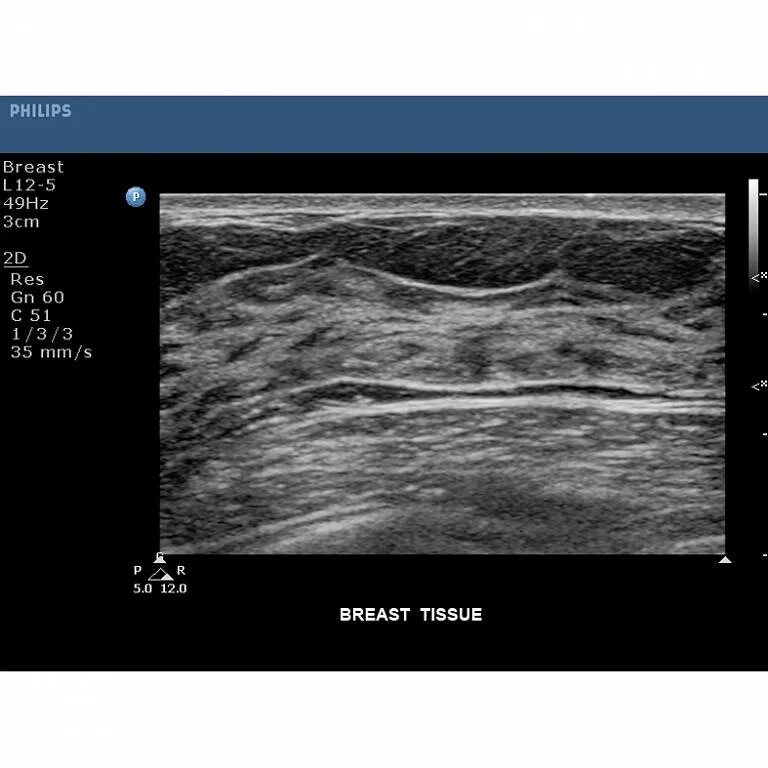

Узи молочных киров